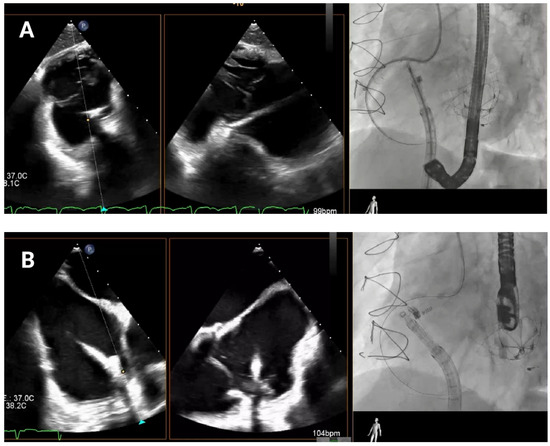

4.4. Band Cinching

In the final release phase of the procedure, the size adjustment tool (SAT) is advanced to contract the Cardioband implant (

Figure 7), a crucial step in securing the device around the tricuspid annulus and effectively reducing the diameter. This reduction is performed in incremental stepwise adjustments, which range between 0 cm and 2.5–3.5–4.5–5.5 cm depending on the chosen band size, to achieve optimal tension and alignment with the annulus. Continuous real-time monitoring with TEE and fluoroscopic imaging is essential during this phase to confirm successful positioning and ensure gradual tightening without impinging on surrounding structures or compromising valve function.

4.5. Final Result Assessment

Post-implantation, comprehensive imaging is used to assess final TR reduction, final transvalvular gradient and assess right ventricular function. Coronary angiography specifically assesses the RCA for any bending or impingement.

Figure 7.

Band cinching and post-implant assessment. The size adjustment tool is used to cinch the Cardioband, reducing the tricuspid annular diameter by 3.5–5.5 cm depending on the band size. Pre-cinching (A) and final result post-cinching (B).